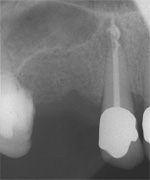

3 Aufnahmen sind von 2001, die vierte vom Nov. 2006

Aufbissempfindlichkeit an 33 veranlasste uns erstmalig in dieser Kieferregion zu röntgen. Mit grossen Augen sahen wir dann an, was uns auch ansah. Einen Knochendefekt dieser Grössenordnung mit seiner schaurigen Aura sieht man zum Glück nicht jeden Tag. Doch, obgleich das Alien dereinst Zahn 34 entsprang, war eine Behandlung nur am Zahn davor durchsetzbar. Dessen Wurzelfüllung erfolgte regulär nach 14 Tagen, neue Terminangebote aber wurden, weil angeblich nicht mehr nötig, verschmäht.

Keine 8 Wochen gingen noch in's Land, bis das mit Macht geschah, was lange schon erwartet war. Das Arbeitsprogramm bestand aus Eröffnung von Zahn 34 und einer Schwellung inkl. Drainage, am nächsten Tag dann noch Aufbereitung des Kanals mit Einlage. 2 Wochen später dann die Füllung plus einem als Resektion deklarierten Auslöffeln des Granu­lationsgewebes durch eine Mini-Öffnung, zu deren Verschluss eine Naht genügte.